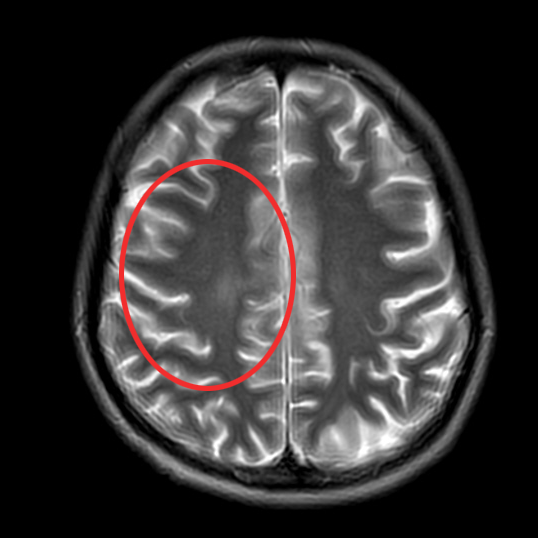

▲治疗后1月

▲治疗后2年半